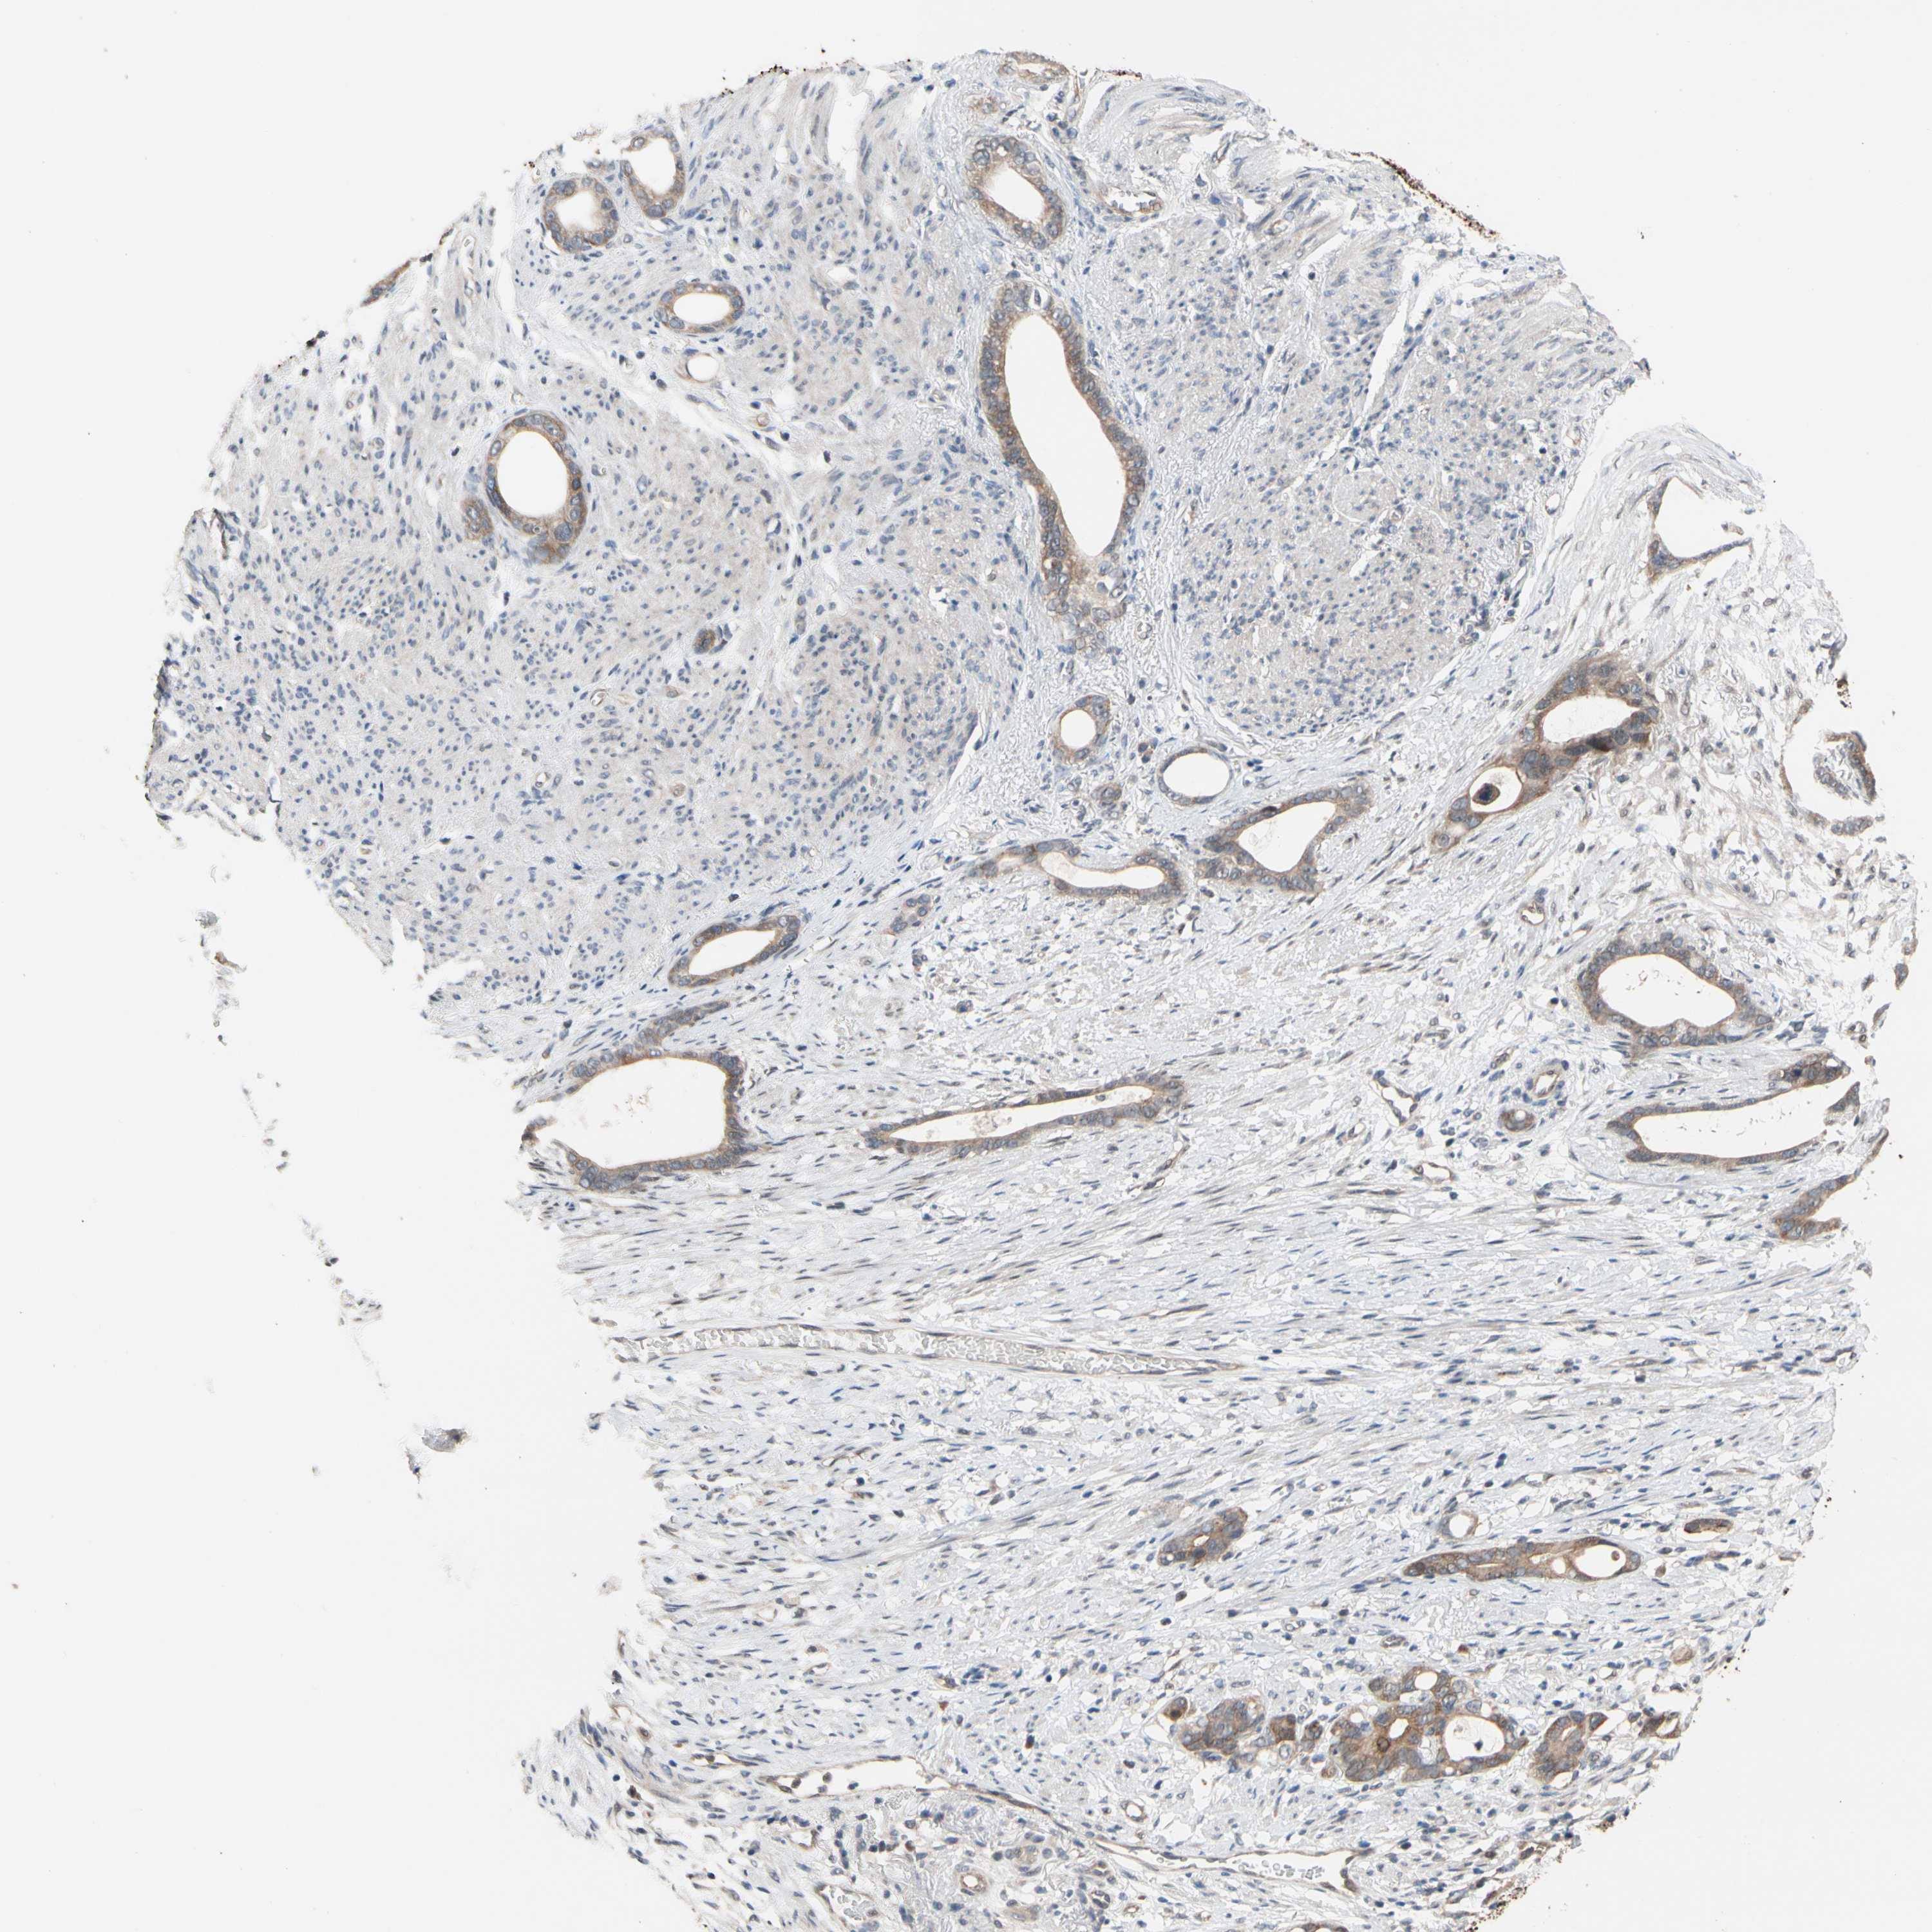

STOMACH CANCER - Protein expressioni

A mouse-over function shows sample information and annotation data. Click on an image to view it in a full screen mode. Samples can be filtered based on level of antibody staining by selecting one or several of the following categories: high, medium, low and not detected. The assay and annotation is described here.

Note that samples used for immunohistochemistry by the Human Protein Atlas do not correspond to samples in the TCGA dataset.

Antibody stainingi

Antibody staining in the annotated cell types in the current human tissue is reported as not detected, low, medium, or high, based on conventional immunohistochemistry profiling in selected tissues. This score is based on the combination of the staining intensity and fraction of stained cells.

Each image is clickable and will lead to virtual microscopy that enables deeper exploration of all samples and also displays staining intensity scores, fraction scores and subcellular localization as well as patient and tissue information for each sample.

Antibody HPA008160

Staining

High

Medium

Low

Not detected

Intensity

Strong

Moderate

Weak

Negative

Quantity

>75%

75%-25%

<25%

None

Location

Nuclear

Cytoplasmic/membranous

Cytoplasmic/membranous,nuclear

Adenocarcinoma, NOS